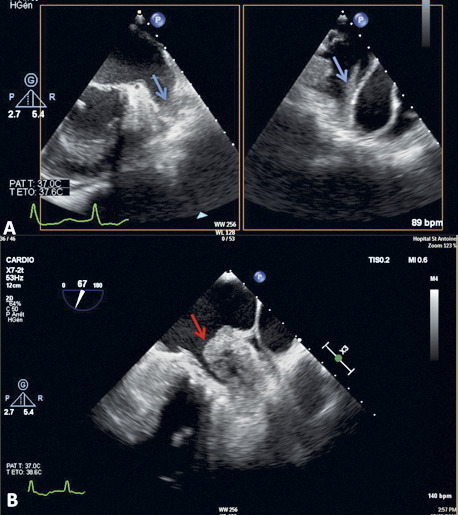

En échocardiographie transœsophagienne (ETO) : on voit mieux l’OG et surtout l’auricule gauche (AG), structure déclive et borgne dans le massif auriculaire, siège électif de la thrombose (90 % des cas hors FA valvulaire).

Sévérité stratifiée selon son intensité (grade 1 à 4), la localisation (OG et/ou AG) et l’éventuel aspect tourbillonnant spontané.

Sludge (grade 4) : stase sanguine préthrombotique caractérisée par du contraste spontané intense donnant un aspect de fumée tourbillonnante mais stagnante au sein de tout ou partie de la cavité auriculaire gauche.

Vitesses de remplissage et de vidange de l’auricule gauche abaissées < 20 cm/s.

Surface de l’AG > 5 cm2.

Thrombus intra-auriculaire gauche, principal déterminant échographique du risque TE artériel.

Recommandée en cas de stratégie de contrôle du rythme par cardioversion électrique chez un patient en FA n’ayant pas reçu d’anticoagulant à doses efficaces pendant au moins 3 semaines. Objectif : éliminer un thrombus ou un sludge, contre-indications à la cardioversion.